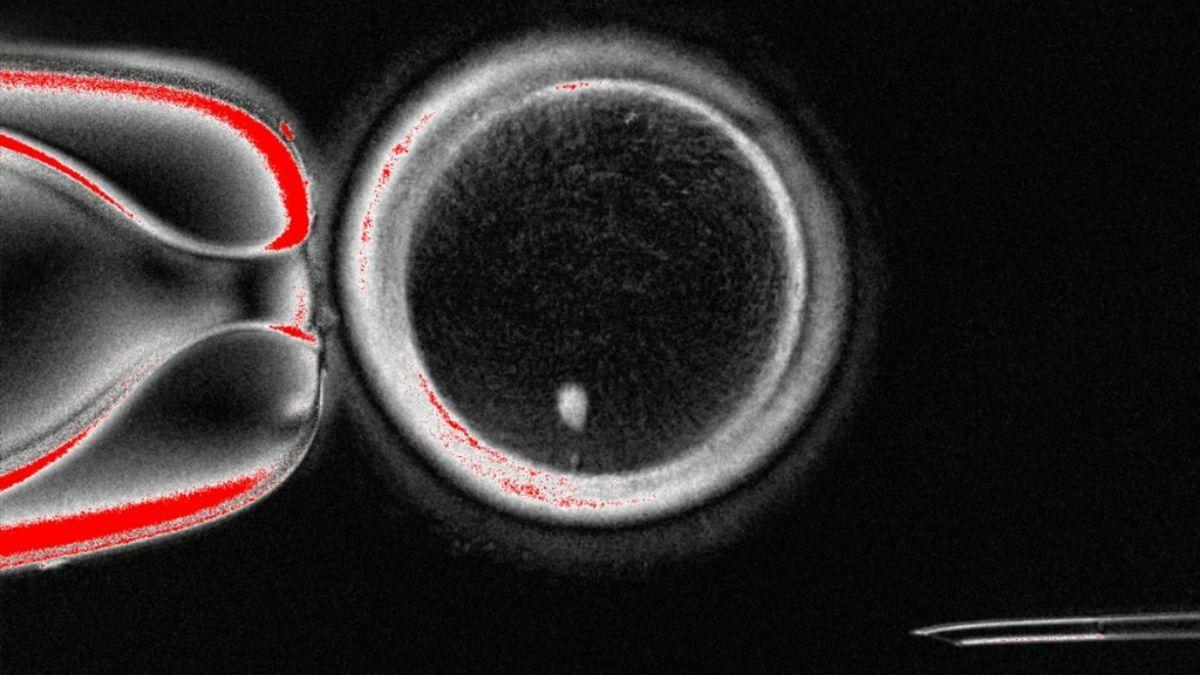

Los investigadores han demostrado una nueva técnica para tratar la infertilidad, convirtiendo las células de la piel en ovocitos u óvulos. Aquí se puede apreciar un ovocito, junto a la imagen brillante del núcleo de una célula de la piel antes de la fertilización. / Crédito: Universidad de Salud y Ciencias de Oregón.

El nuevo estudio, publicado hoy en la revista Nature Communications, describe cómo células cutáneas fueron transformadas y usadas para crear ovocitos, que luego fueron fertilizados in vitro. La técnica consiste en la incorporación del núcleo de una célula de la piel en un óvulo donante, que había sido previamente despojado de su propio núcleo.